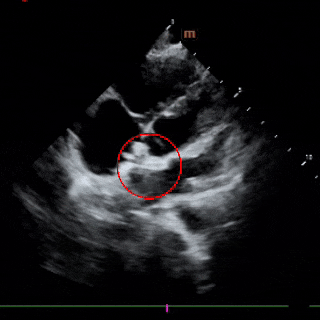

超声所见:

1、各房室腔内径正常,大动脉内径及位置关系正常。

2、室间隔及左室后壁厚度及运动幅度正常。多切面显示房间隔中部可见宽约5mm的回声失落,多普勒示左向右分流束,流速约122cm/s,室间隔连续。

3、CDFI示三尖瓣见少量反流,流速约275cm/s,估测肺动脉收缩压约35mmHg;二尖瓣见少量反流,反流面积约1.0cm2;肺动脉瓣见小反流束。

4、心包厚度正常,心包腔内未见液性暗区。

5、心功能测值正常。

超声提示:房间隔中部回声失落,考虑:房间隔缺损;三尖瓣、二尖瓣少量反流;肺动脉轻度高压。

术中复测

左室长轴切面及四腔心切面复测缺损直径均约6mm